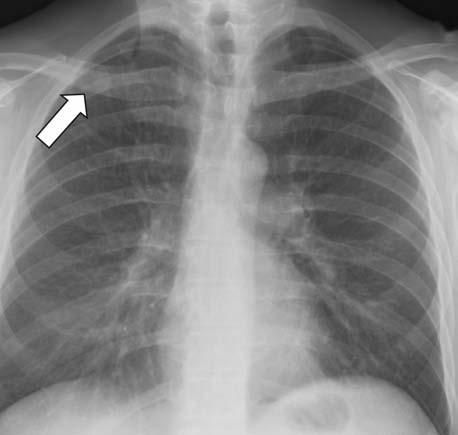

Laboratory evaluation revealed a normal complete blood cell count but mildly elevated levels of transaminases. A chest radiograph revealed a 2-cm cavitary right upper lobe (RUL) lesion (Figure 1). CT scans of the chest and abdomen revealed the solitary lung lesion, on a background of centrilobular emphysema (Figure 2), and bilateral non-homogeneous adrenal glands, with the left gland appearing larger than the right one (Figure 3). CT scans did not reveal any mediastinal lymphadenopathy or pleural effusions.

Figure 1 – A cavitary upper lobe mass appears behind the right clavicle in this posteroanterior chest radiograph (arrow).